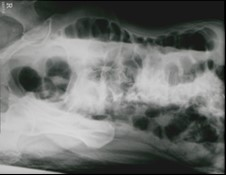

Które badanie zostało zarejestrowane na przedstawionym radiogramie?

Ilustracja do pytania 21

A. Jamy brzusznej wykonane poziomą wiązką promieniowania.

B. Płuc wykonane metodą Przybylskiego.

C. Układu moczowego z użyciem środka kontrastującego.

D. Dróg żółciowych metodą cholangiografii śródoperacyjnej.